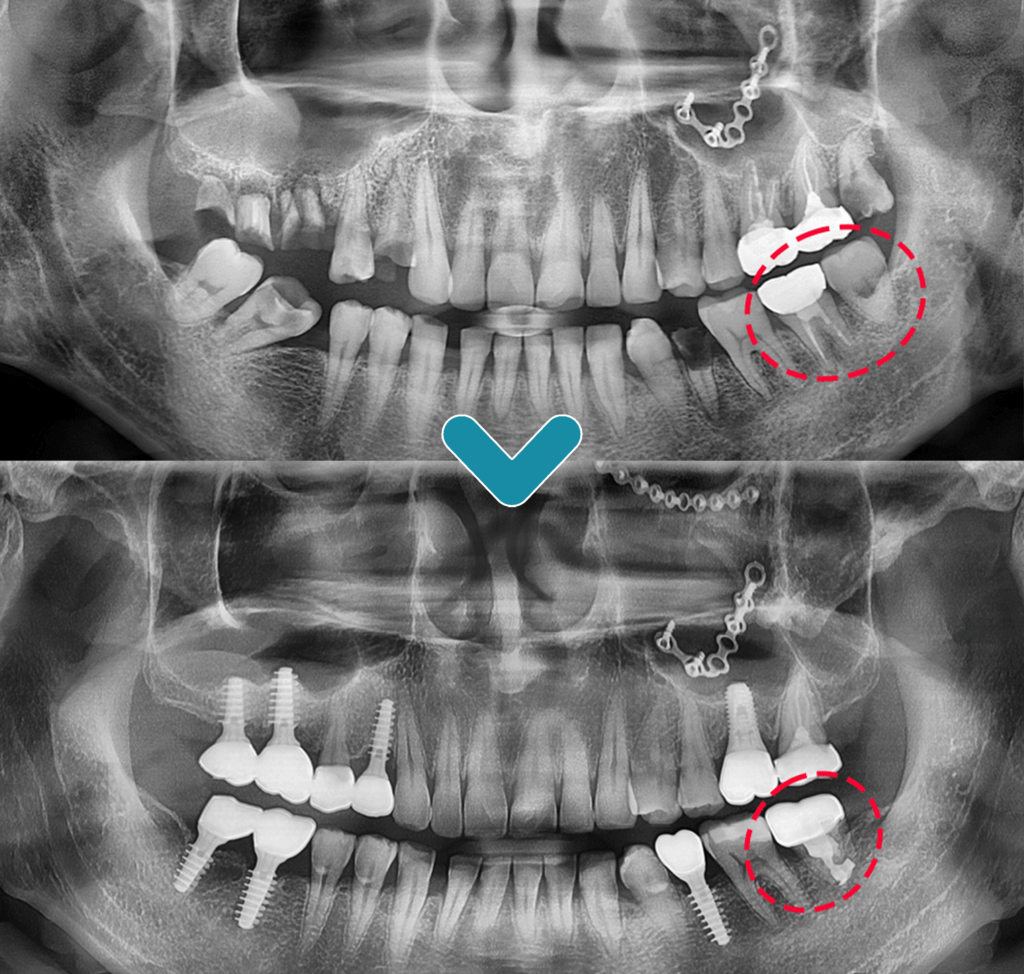

오늘은 사랑니를 어금니로 이식하는

치아이식술을 진행한 사례를

소개해드리겠습니다. : )

예후가 좋지 않은 어금니를 발치한 후

사랑니를 그 자리에 이식하는

치아이식술을 진행하기로 치료 계획을 세웠습니다.

사랑니를 어금니 부위에 이식한 뒤

크라운으로 덮어 5년이 지난 후에도

문제없이 잘 사용하는 중입니다. : )